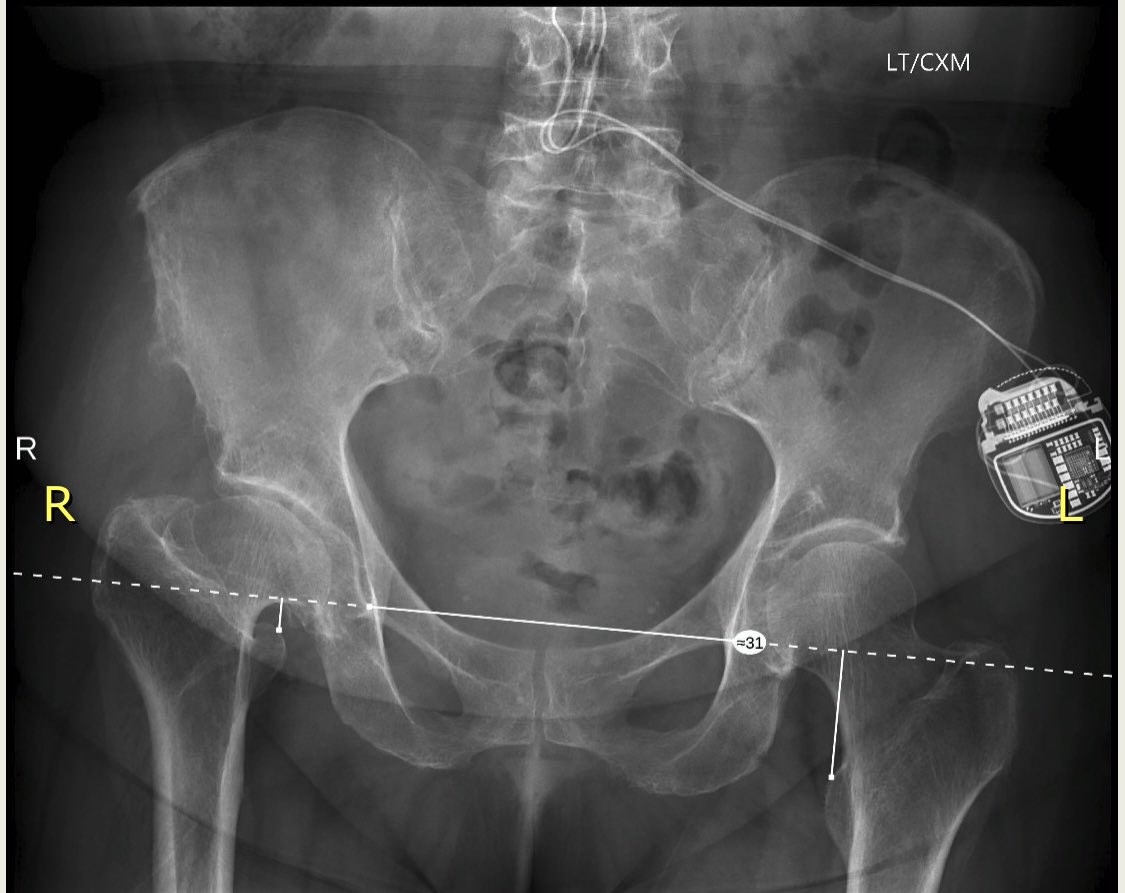

Female 67 y/o - THA

*Approach?

*What stem do you choose?

*Comments & tricks?

@AAHKS_YAG @AAHKS_YAG @JArthroplasty @AAOS1 @CleClinicArthGp